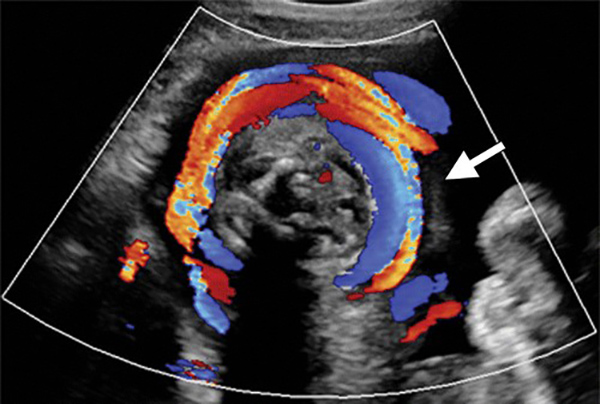

Hình ảnh siêu âm dây rốn quấn cổ

Qua hình ảnh siêu âm đen trắng, khả năng phát hiện ra dây rốn quấn cổ là 70%, với siêu âm Doppler màu, độ chính xác từ 83 – 97%. Siêu âm là cách giúp xác định dây rốn có quấn cổ hay không, quấn mấy vòng, nhưng không thể can thiệp để tháo dây rốn.